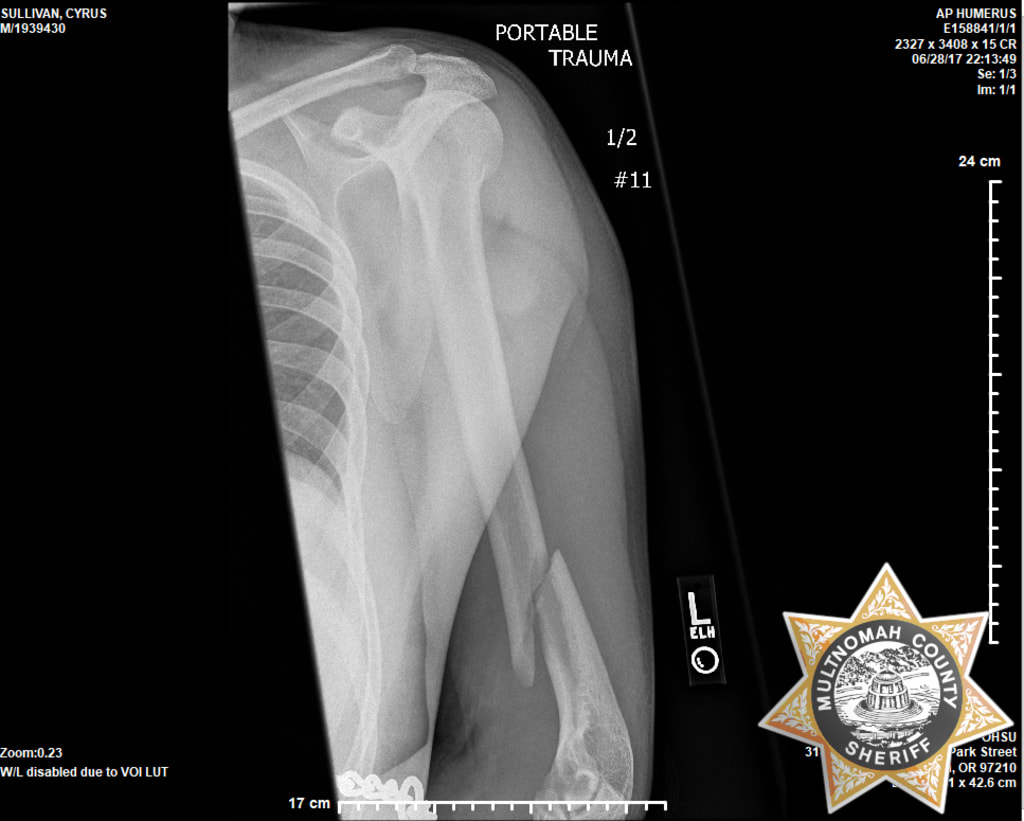

Multnomah County recently settled a federal lawsuit with the founder of a police misconduct reporting website which he filed as his own attorney over the breaking of his left arm at the hands of correctional deputies in 2017. CopBlaster.com founder Cyrus Sullivan or Portland, Oregon subsequently pled guilty to one count of assaulting a federal officer for how he provoked the deputies but always insisted his arm was broken intentionally after the fact.

What happened after Sullivan threw chips has been the subject of debate ever since due to a lack of video evidence. Every deputy involved claimed Sullivan's arm was broken during the cell extraction while Sullivan always maintained that his arm was broken in the disciplinary unit on the floor below after transport was complete while he was pinned face down to mattress.

Sullivan's lawyers retained the services of biomechanics expert Dr. Wilson "Toby" Hayes to prove that Sullivan's explanation is the only explanation scientifically capable of explaining his injury. Dr. Hayes' expert witness report was dumped on the prosecution just a couple weeks before trial after which Sullivan was quickly offered time served if he pled guilty to the lesser charge of assault with physical contact and no injury in violation of 18 U.S.C.(a)(1) under the reasonable apprehension of harm prong.

Sullivan was taken to his outside follow up a month late and denied a proper brace which would have made his recovery less painful. The brace known as a "Sarmiento Brace" would have stopped his bone from moving as much and may have resulted in it healing at a better angle.

Broken arms without surgery do not produce significant medical bills. Typically medical bills are multiplied by a number between 1.5 and 5 based on severity of the injury to determine pain and suffering (See Forbes pain and suffering calculator). Sullivan would be surprised if the county spent more than $5,000 on his care and wouldn't give his injury a severity score of more than 4 or possibly 4.5 due to pain. That produces a range between $20,000 and $22,000 but Sullivan believes the county likely spent less than $4,000. An ambulance ride, ER visit with x-rays, follow-up with x-rays, and in house appointments are not terribly expensive.